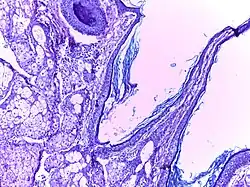

![]() | Benign cystic teratoma | Micrograph of Teratoma Ovary showing areas of cartilage, mucous glands, squamous epithelium and hair follicle. | Category: Histopathology of mature teratoma of ovary | teratoma |